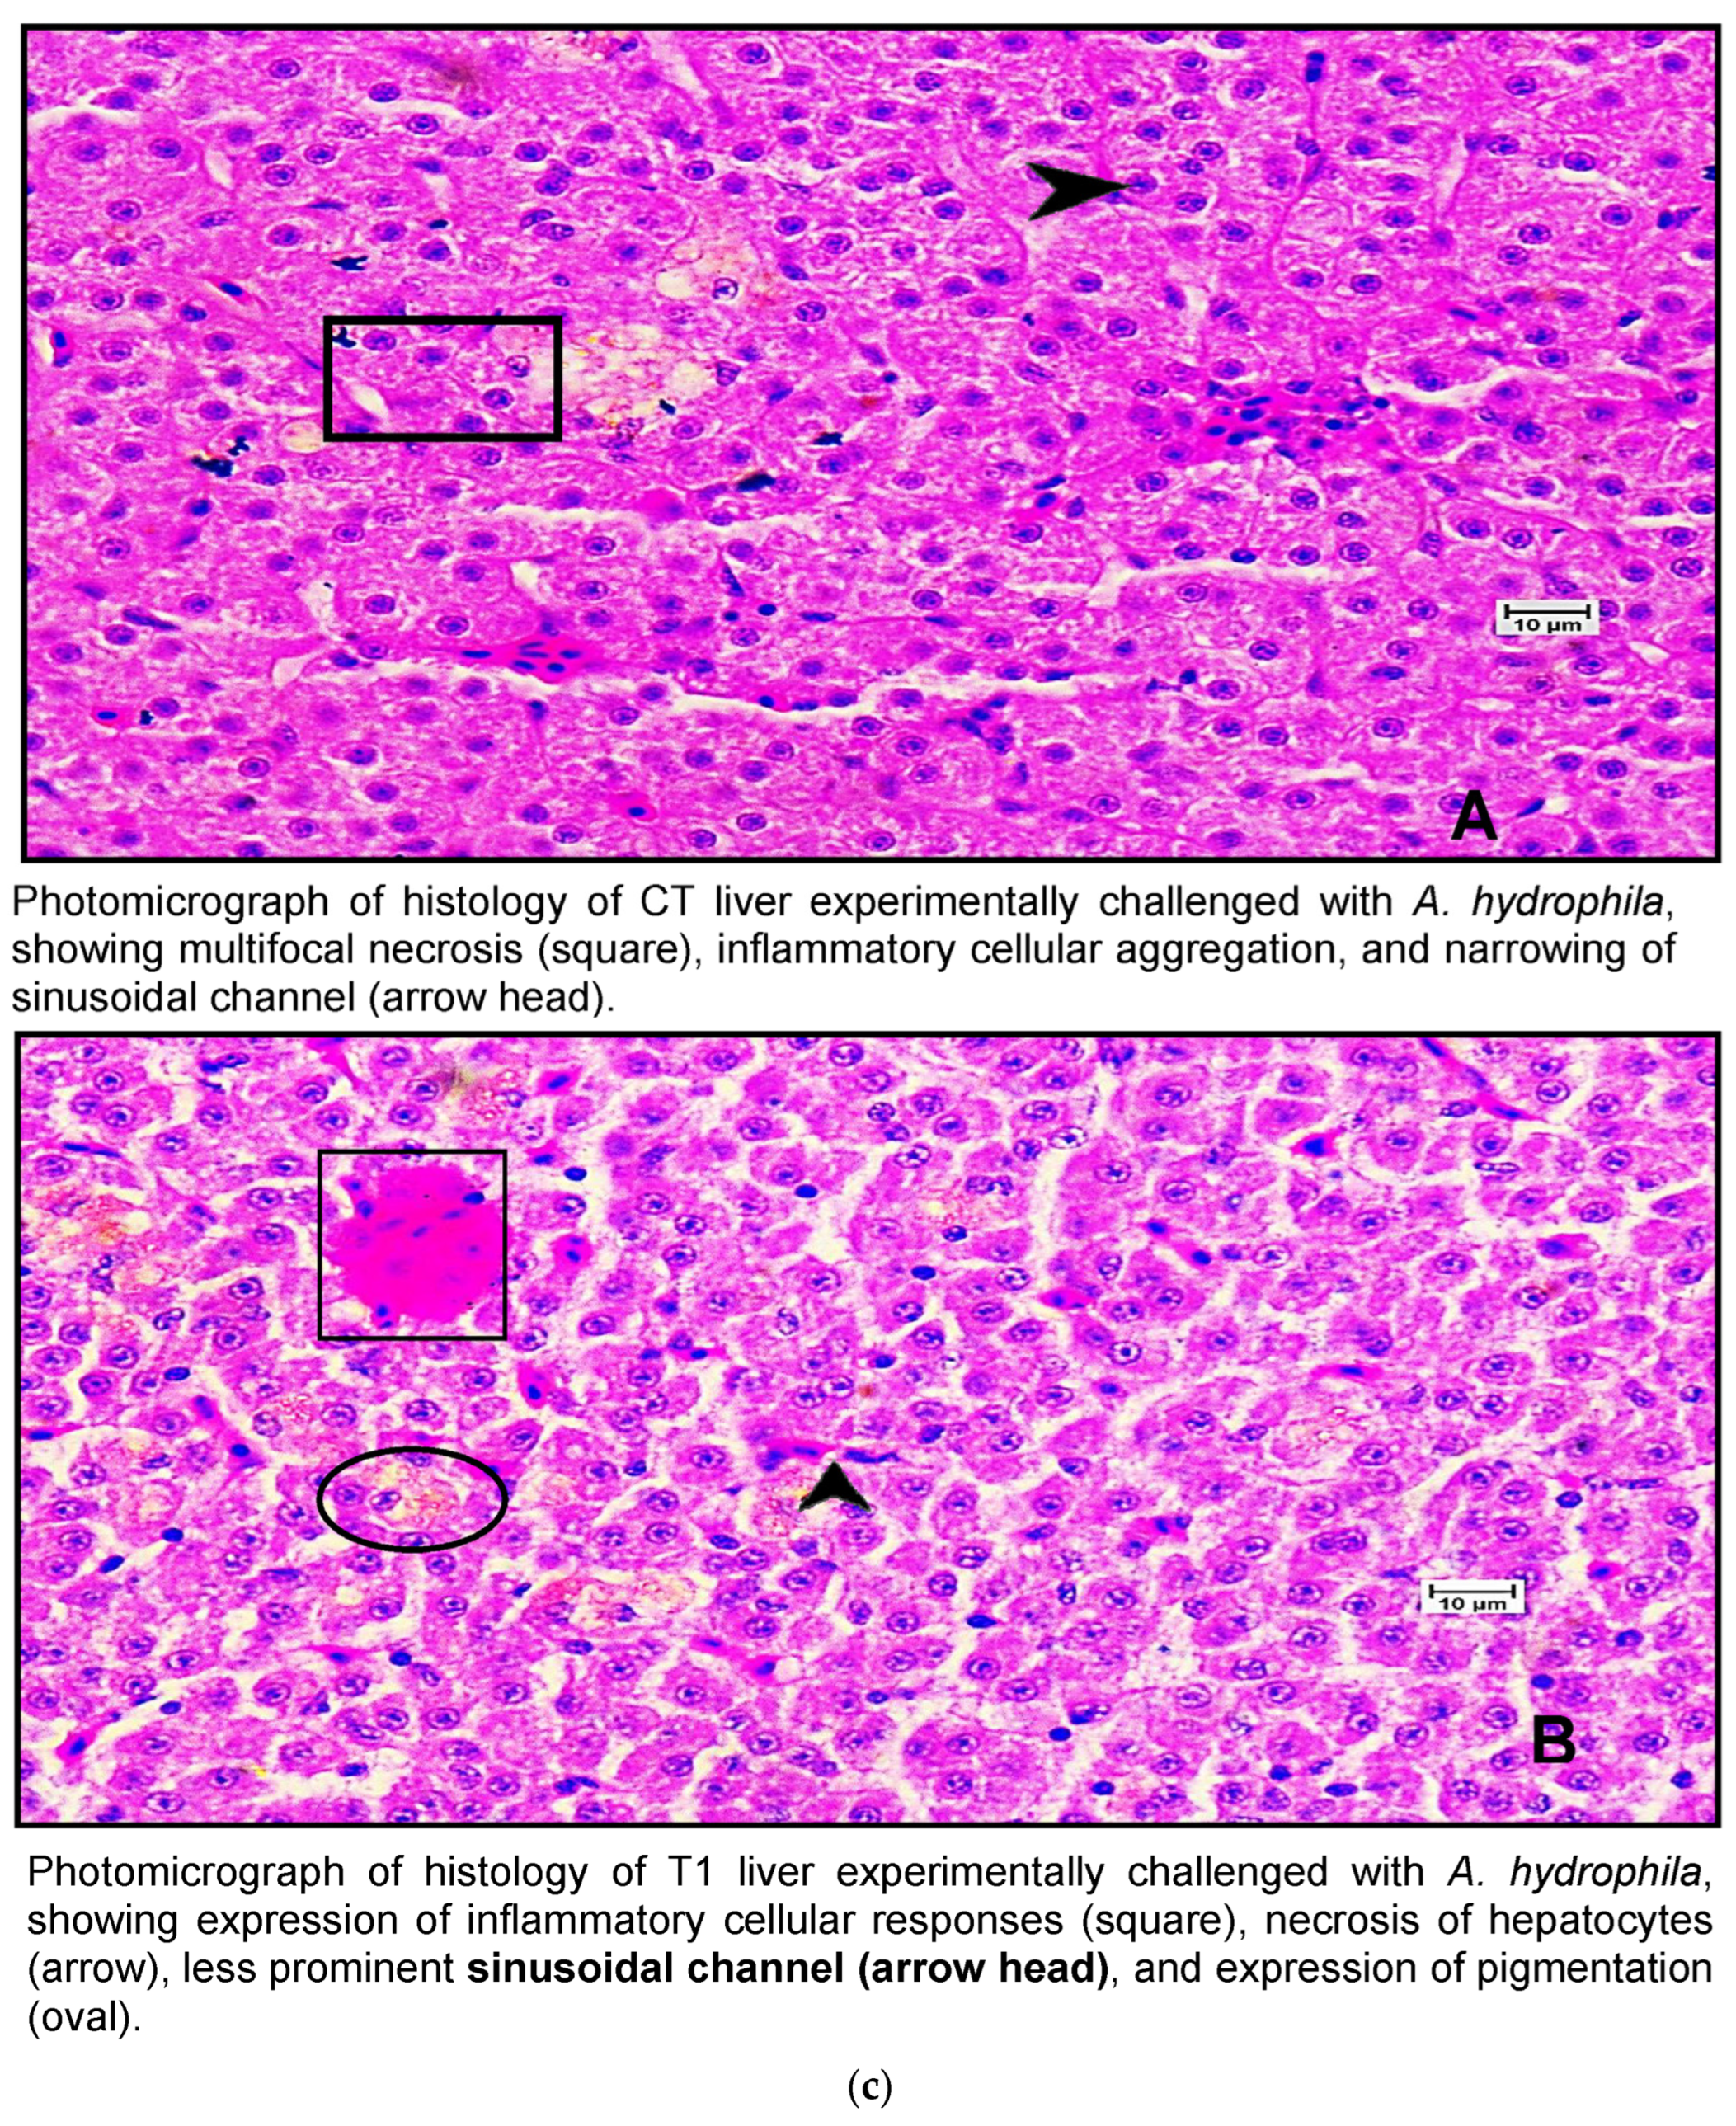

Histological examination of the livers of fish fed the control diet (CT) and the high-dose TABP diet (T3) revealed significant differences in the liver pathology (Figure 7a,b). The livers of fish fed the CT diet had a normal organization of polygonal hepatocytes, normal bile duct, and central vein. In contrast, the livers of fish fed the T3 diet showed fibrosis with fat deposits and altered the normal architecture of the hepatocytes. These findings are consistent with previous studies that have shown that high doses of TABP can cause liver damage in fish. The liver is a vital organ for fish, as it plays a role in digestion, absorption, metabolism, and detoxification. Liver damage can lead to a number of problems, including impaired growth, decreased reproduction, and increased susceptibility to disease. The findings of this study suggest that high doses of TABP can cause liver damage in fish, and further research is needed to determine the safe level of exposure for fish. In addition to the histological changes, the fish fed the T3 diet also had increased levels of oxidative stress markers in the liver. Oxidative stress is a condition that occurs when there is an imbalance between the production of free radicals and the body’s ability to remove them. Free radicals are unstable molecules that can damage cells and tissues. The increased levels of oxidative stress markers in the fish fed the T3 diet suggest that TABP may be causing oxidative stress in the liver, which could contribute to the liver damage observed in this study. The findings of this study provide evidence that high doses of TABP can cause liver damage in fish. Further research is needed to determine the safe level of exposure for fish and to identify the mechanisms by which TABP causes liver damage.

Figure 7.

(a) A photomicrograph of the livers of CT and T1 groups. (b) A photomicrograh of the livers of T2 and T3. (c) A photomicrograph of the livers of CT and T1 groups challenged with A. hydrophila. (d) A photomicrograph of the livers of T2 and T3 groups challenged with A. hydrophila. (e) A photomicrograph of the livers of CT and T1 infected with E. tarda. (f) A photomicrograph of the histology of the liver of T2 and T3 infected with E. tarda.